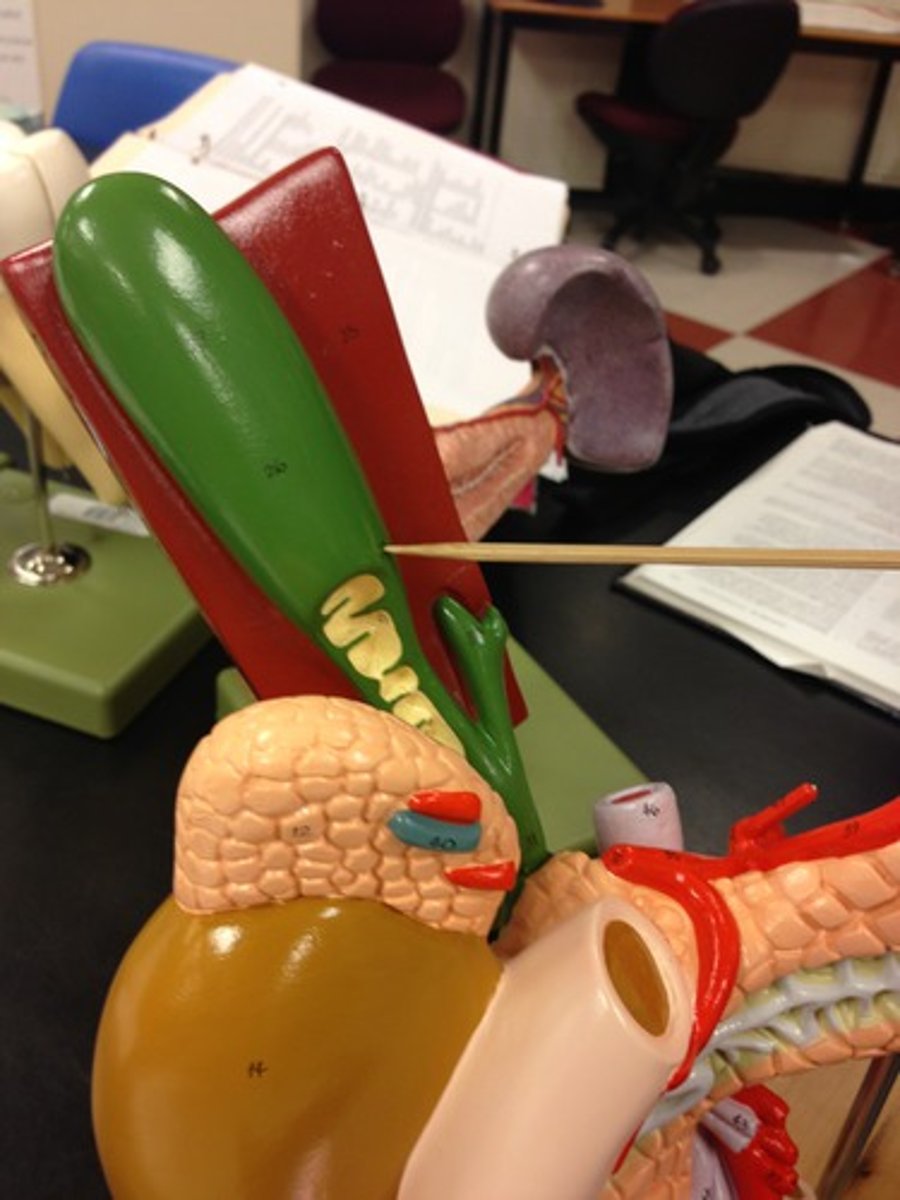

head (of pancreas)

body (of pancreas)

tail (of pancreas)

main pancreatic duct

accessory pancreatic duct

hepatopancreatic ampulla

pancreatic + bile duct

gallbladder